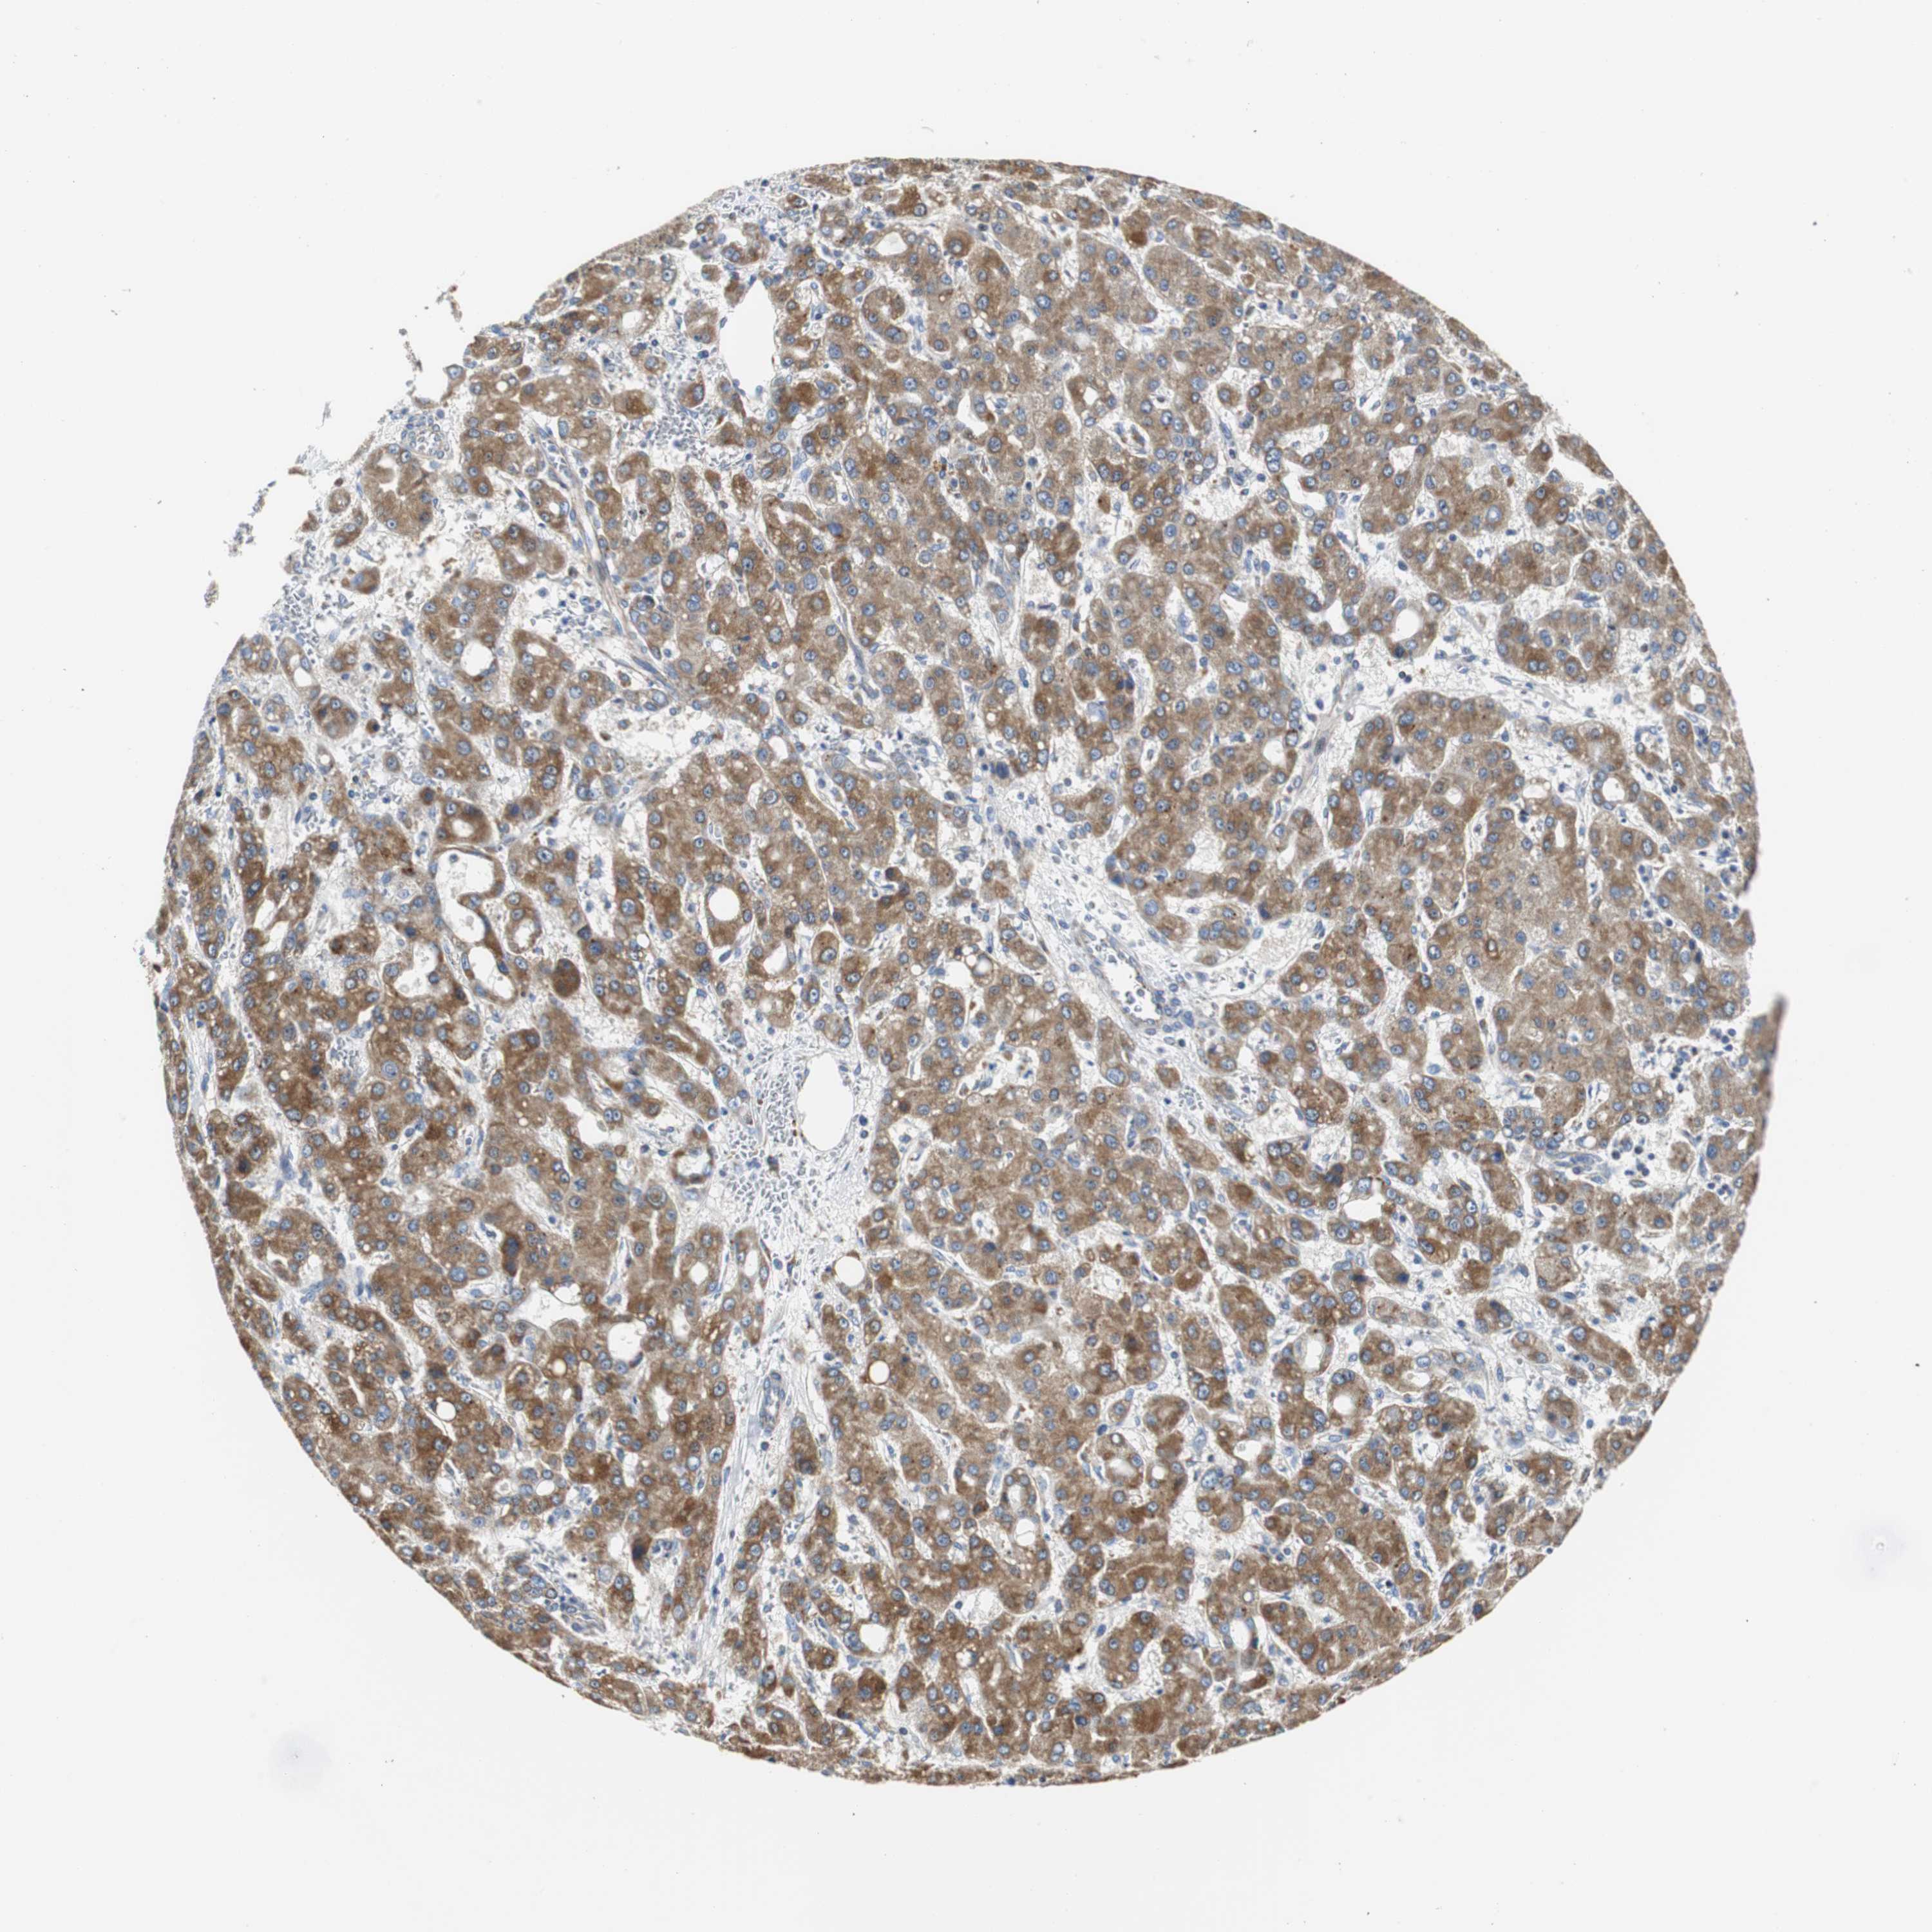

LIVER CANCER - Protein expressioni

A mouse-over function shows sample information and annotation data. Click on an image to view it in a full screen mode. Samples can be filtered based on level of antibody staining by selecting one or several of the following categories: high, medium, low and not detected. The assay and annotation is described here.

Note that samples used for immunohistochemistry by the Human Protein Atlas do not correspond to samples in the TCGA dataset.

Antibody stainingi

Antibody staining in the annotated cell types in the current human tissue is reported as not detected, low, medium, or high, based on conventional immunohistochemistry profiling in selected tissues. This score is based on the combination of the staining intensity and fraction of stained cells.

Each image is clickable and will lead to virtual microscopy that enables deeper exploration of all samples and also displays staining intensity scores, fraction scores and subcellular localization as well as patient and tissue information for each sample.

Antibody HPA006277

Antibody HPA006507

Antibody CAB017027

Staining

High

Medium

Low

Not detected

Intensity

Strong

Moderate

Weak

Negative

Quantity

>75%

75%-25%

<25%

None

Location

Nuclear

Cytoplasmic/membranous

Cytoplasmic/membranous,nuclear

Cholangiocarcinoma

Carcinoma, Hepatocellular, NOS